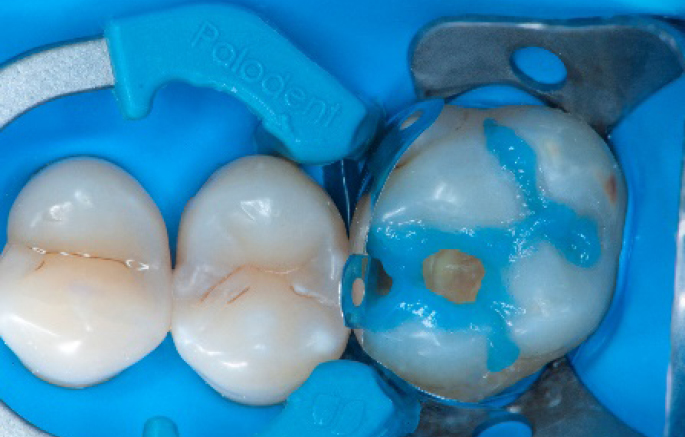

Step 1:

The situation after rubber dam isolation.

Step 6:

Selective enamel etching procedure with Conditioner2.